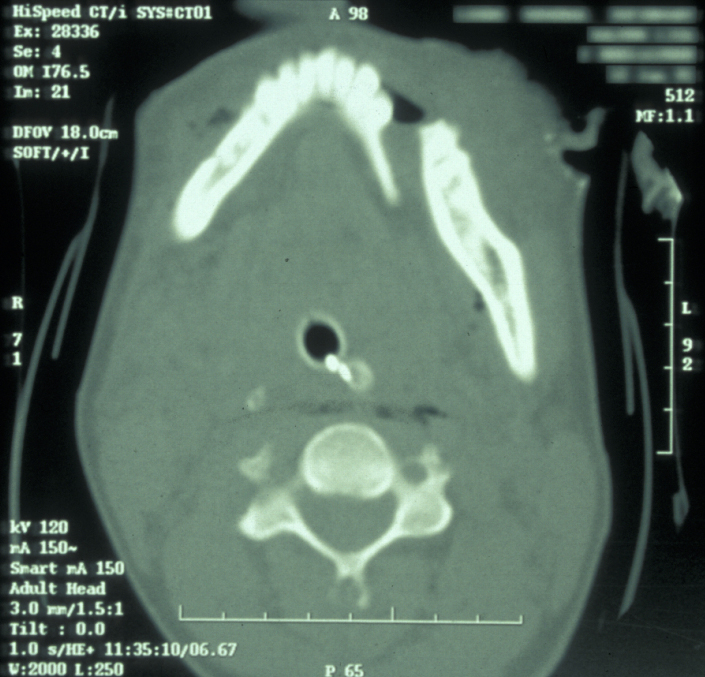

If the patient is unable to stand in the DPT machine, left and right lateral oblique mandibular views will give good imaging of the body of the mandible.  If the patient has multiple complex maxillofacial fractures a CT scan (CT coronal and axial images, with or without 3D reformatting) is helpful (see Figure 4). The CT scan will help assess condylar fracture position, angulation and any fractured dislocation of the condylar head. A CT scan is also useful to image multi-part mandibular body fractures.

Figure 4: CT scan of a displaced mandibular fracture.